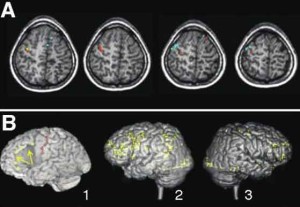

Pruessner e colleghi hanno studiato – grazie al protocollo “Montreal Imaging Stress Task” (MIST) da loro stessi sviluppato e basato sulla tecnica di risonanza magnetica funzionale – l’attività cerebrale di un gruppo di volontari in salute vissuti in aree sia urbane sia rurali.

L’analisi dei dati raccolti ha mostrato come la vita in città fosse associata a una più intensa risposta di stress dell’amigdala, un’area del cervello coinvolta nella regolazione emotiva e nell’umore. Inoltre, l’essere cresciuti in un contesto urbano è risultato associato all’attività della corteccia cingolata, una regione coinvolta nella regolazione degli stati affettivi negativi e dello stress.